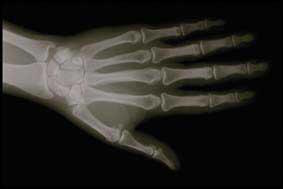

Glucosamine et arthrite

La glucosamine semble renforcer le soulagement de la douleur apporté par l'ibuprofène. Dans cette étude réalisée sur des souris de laboratoire, des chercheurs ont testé différentes doses de glucosamine et différents anti-inflammatoires non stéroïdiens (AINS). L'administration d'AINS seuls soulageait la douleur mais ce n'était pas le cas lorsque l'on donnait uniquement de la glucosamine aux animaux.

Ces dernières années la glucosamine a fait l'objet de nombreuses études comme traitement de l'arthrite. Celles-ci ont montré qu'elle soulageait de façon importante les problèmes de mobilité chez les patients souffrant d'arthrite. Elle aide à ralentir la détérioration des os, à réparer les lésions sur les os et les cartilages ainsi qu'à réduire l'inflammation. Cependant aucune étude n'a regardé si la glucosamine pouvait stopper la douleur.

Dans cette étude, lorsqu'elle était associée à l'ibuprofène, la glucosamine apportait un soulagement de la douleur plus prononcé que ne le faisait l'ibuprofène seul. Actuellement, des études cliniques examinent la possibilité qu'un mélange contenant certains ratios de glucosamine et certains AINS puisse renforcer le soulagement de la douleur chez des patients souffrant d'arthrite ou que l'on puisse obtenir un niveau acceptable de soulagement de la douleur avec de plus faibles doses d'AINS.